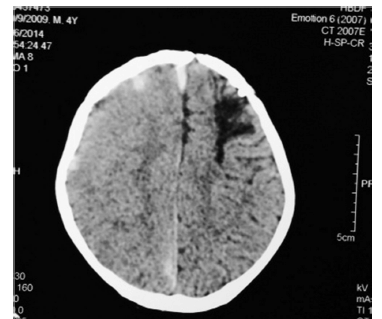

Observe a figura a seguir.

Paciente com quatro anos de idade, portador de hemofilia A, com inibidor de alta resposta em alto título (60 unidades Bethesda), apresenta, há 15 dias, queda da própria altura, quadro de náusea, cefaleia e crise convulsiva. A imagem da tomografia de crânio sem contraste mostra-se com o aspecto apresentado na figura. Nessa situação hipotética, o tipo de terapia indicado para o tratamento de urgência do paciente é a reposição de